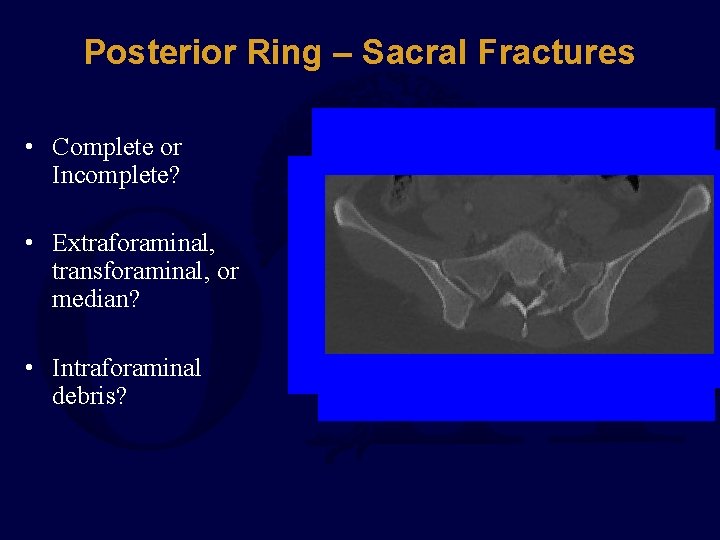

Posterior Ring – Sacral Fractures • Complete or Incomplete? • Extraforaminal, transforaminal, or median? • Intraforaminal debris?